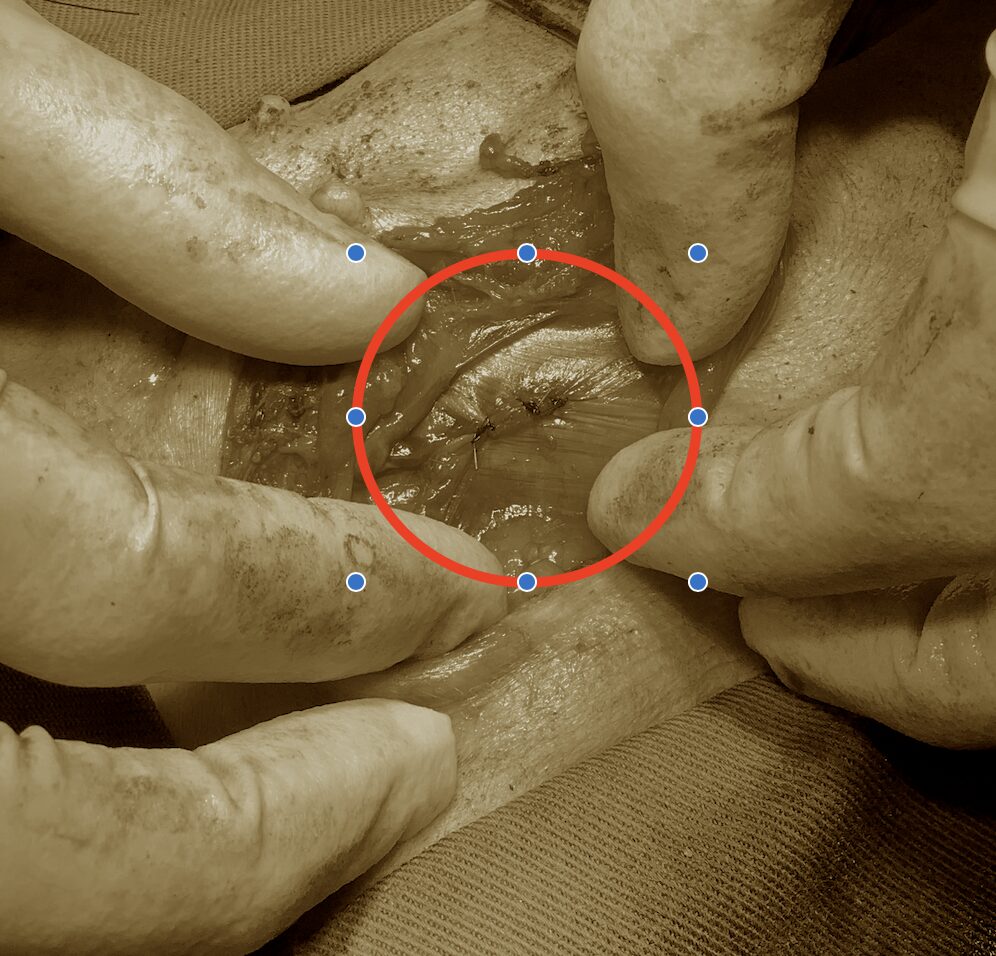

手術を行いました。

重要な動脈や静脈、神経も出てきているのでそれらを絞扼しないように気をつけて縫合をしました。